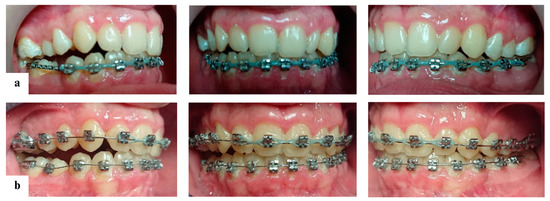

2.3. Treatment Progress